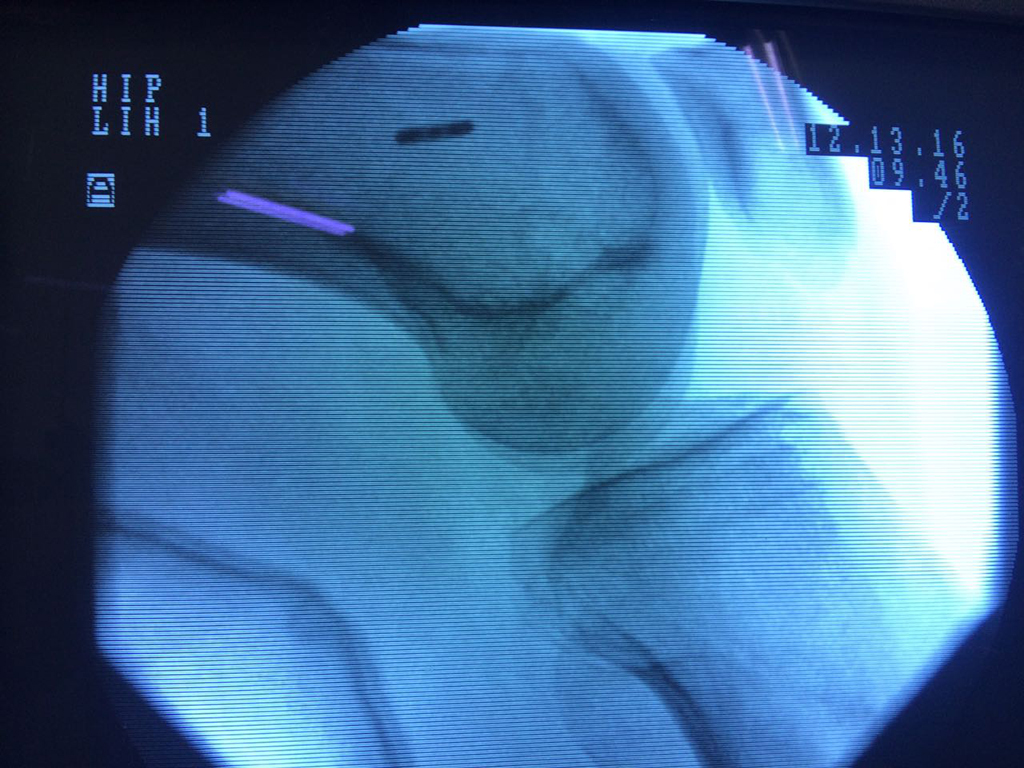

Cirugías de Rodillas

La artroscopia de rodilla es un cirugía en el cual la estructura interna de la articulación es examinada ya sea para realizar un diagnostico o para realizar un tratamiento, este procedimiento se realiza utilizando un instrumento parecido a un pequeño tubo llamado artroscopio.